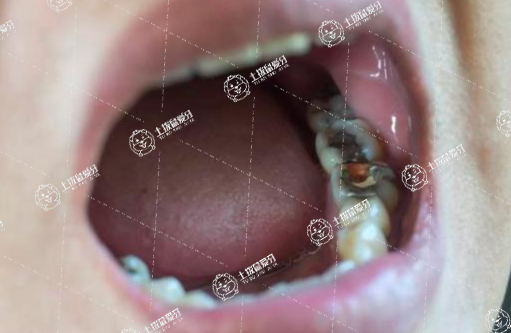

如果小孩子牙齒出現(xiàn)了病變,有蛀牙,有牙神經疼痛,有牙根的炎癥,這種情況都是需要進行干預治療的。蛀牙要做補牙治療。

神經疼痛或者是牙根炎癥疼痛,要做乳牙的根管治療,根管治療之后再做補牙。

所以小孩子是可以做補牙的,而且是必須做補牙,一旦發(fā)生病變,需要補牙,無論是小孩子的乳牙還是替牙期的恒牙,都是需要做補牙的。